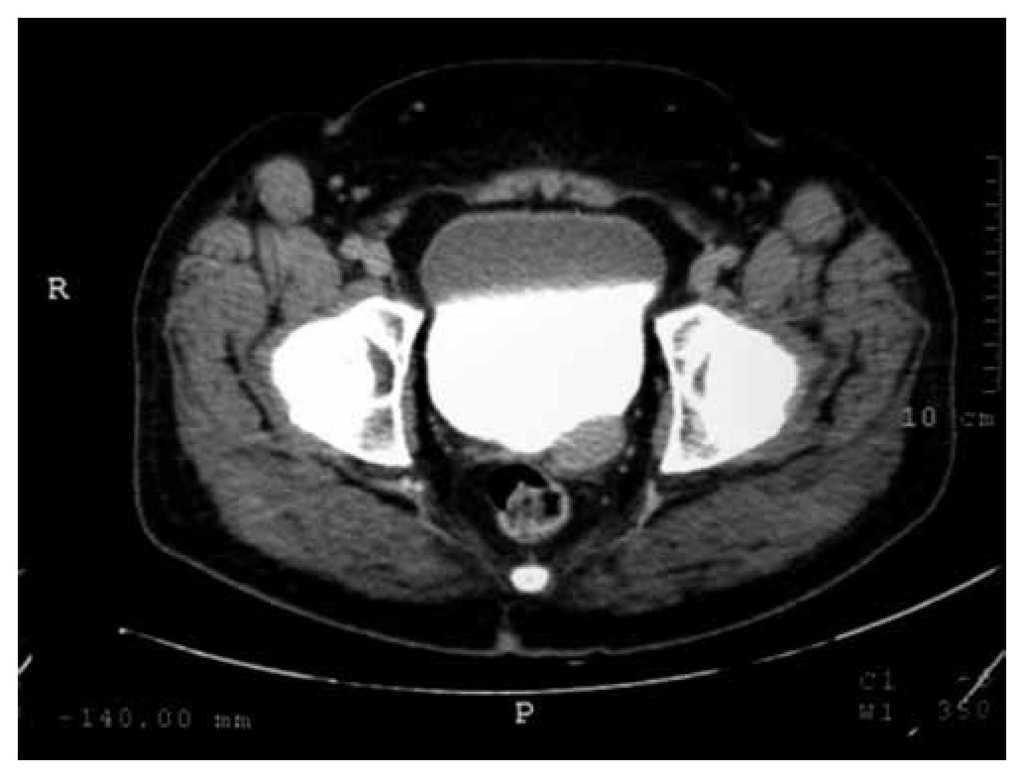

Hombre de 37 años de edad, con antecedente de diabetes mellitus tipo 2, tratado con insulina (20 U de intermedia y 15 U de rápida). El padecimiento actual inició 7 días previos a acudir a valoración, consistente en dolor lumbar irradiado a flanco y fosa ilíaca izquierda, tipo cólico, de moderada intensidad, continúo. Al examen físico, tacto rectal con próstata adenomatosa grado 1, no sospechosa. Se realizó ultrasonido (USG) renal y suprapúbico, donde se encontró imagen sugestiva de lesión paravesical izquierda, hiperecoica, homogénea, de bordes bien definidos, de 2 x 2 cm (fig. 1). La urotomografía (UroTAC) corrobora imagen de lesión, con densidad sólida entre base de vejiga y vesícula seminal izquierda de 3 x 2 cm (figs. 2 y 3). El USG transrectal con lesión dependiente de vesícula seminal izquierda (fig. 1). En la cistoscopía diagnóstica se encontró compresión extrínseca parameatal izquierda. Se llevó a cabo resección de neoplasia de vesícula seminal izquierda por vía laparoscópica de 3 x 2 cm (fig. 4), con resultado de histopatología de leiomioma de vesícula seminal. El paciente se encuentra en seguimiento con buena evolución.

Figura 2 Tomografía computada simple. Es clara la imagen donde se aprecia una lesión en la base lateral izquierda de la vejiga.